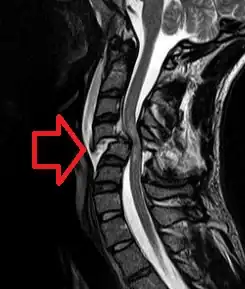

MRI of a fractured and dislocated cervical vertebra (C4) in the neck that is compressing the spinal cord

In the majority of cases the damage results from physical trauma such as car accidents, gunshot wounds, falls, or sports injuries, but it can also result from nontraumatic causes such as infection, insufficient blood flow, and tumors. Just over half of injuries affect the cervical spine, while 15% occur in each of the thoracic spine, border between the thoracic and lumbar spine, and lumbar spine alone.[1] Diagnosis is typically based on symptoms and medical imaging.[1]